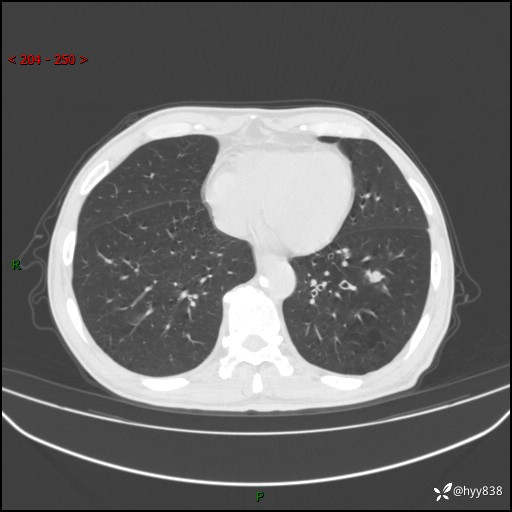

辅助检查:CT

讨论:结节性质?

增强动脉期+静脉期

各期CT值:38Hu 52hu 55hu